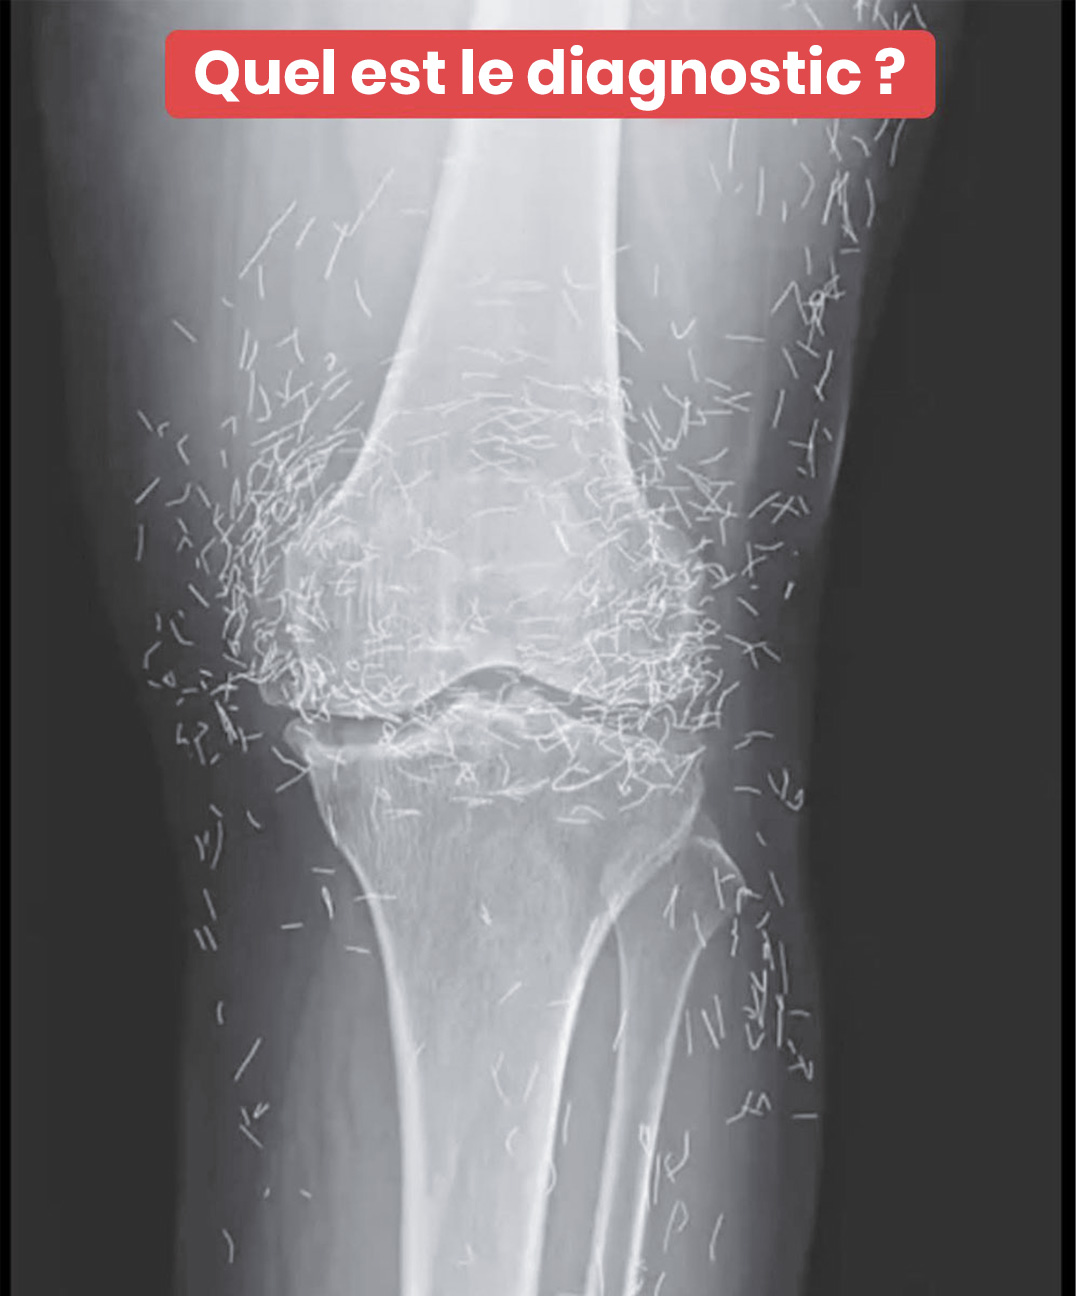

C’est lors d’un examen d’imagerie classique que les médecins ont découvert, étonnés, des centaines de petites pointes brillantes dispersées autour de son genou. Une singularité médicale qui a suscité autant d’étonnement que de questions. Car si l’or est bien toléré par le corps, la présence d’éléments étrangers n’est jamais sans risque.

D’après des spécialistes en radiologie, ces implants métalliques peuvent masquer certaines structures sur les clichés radiologiques, ce qui complique le diagnostic d’autres problèmes. Plus inquiétant encore, ils rendent difficile la réalisation d’une IRM : le champ magnétique pourrait déplacer les aiguules et causer des lésions aux tissus.